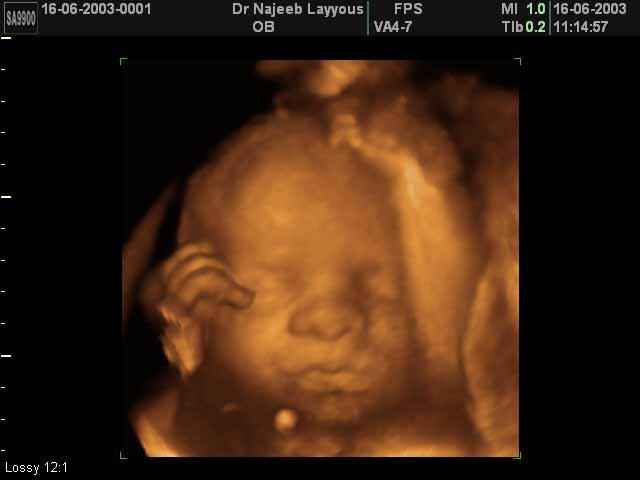

3D Fetal Face Ultrasound Scan Photos